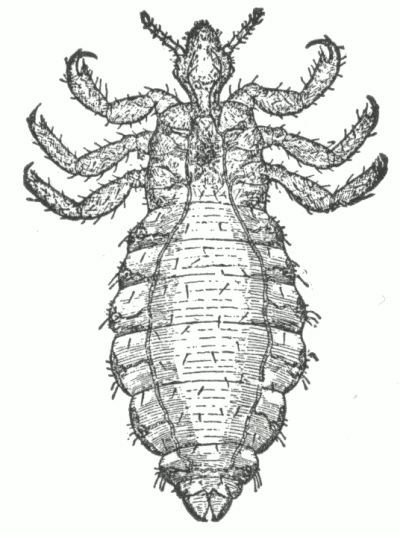

Fig. 6.

A normal sweat-gland, highly magnified. (After Neumann.)

a, Sweat-coil: b, sweat-duct; c, lumen of duct; d, connective-tissue capsule; e and f, arterial trunk and capillaries.